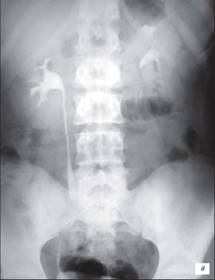

Екскреторна урографія хворого з двостороннім обструктивним мегауретритом

На екскреторній урографії ми спостерігаємо збільшення мисочок, розширення сечоводів, і змінену форму сечового міхура. Стінки якого мають бугристу, нерівну поверхню.